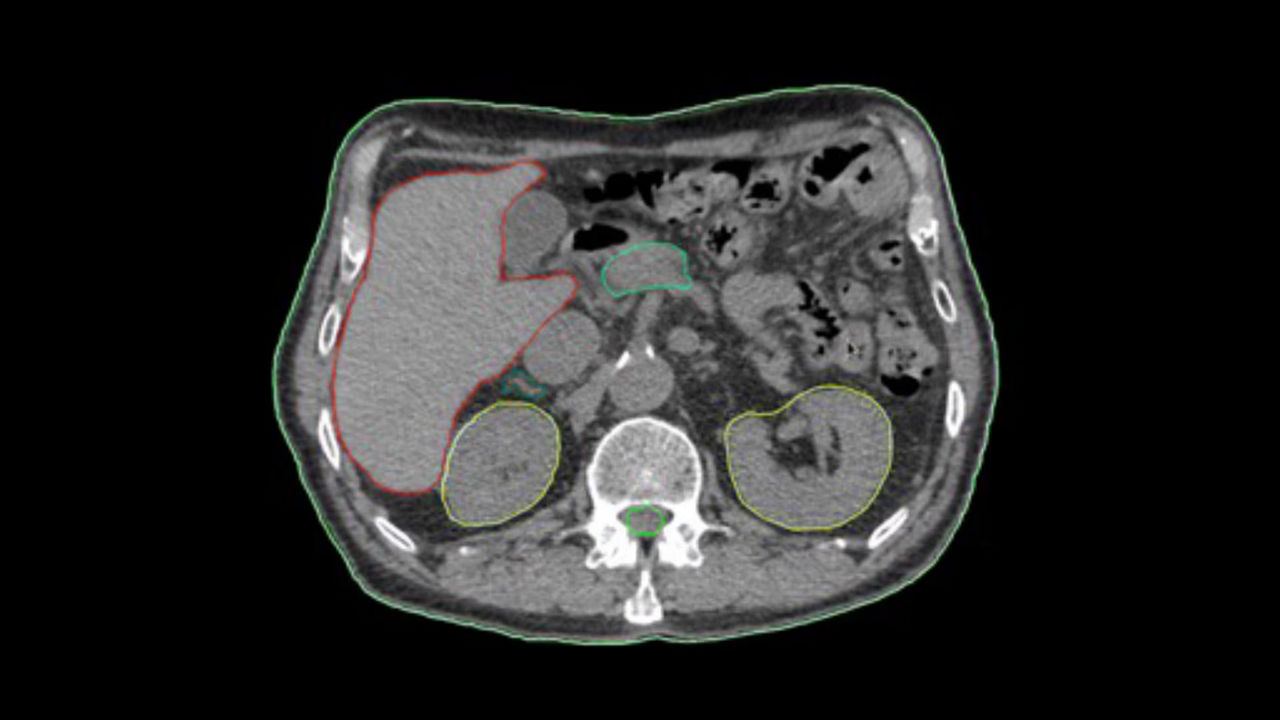

Enable spectral imaging studies and simplify the reading and analysis of spectral datasets.

<p>GSI Xtream/GSI Pro</p>

<p>Spectral Auto Views</p>

Learn more

<p>GSI Viewer</p>

<p>Thoracic VCAR with GSI Pulmonary Perfusion</p>